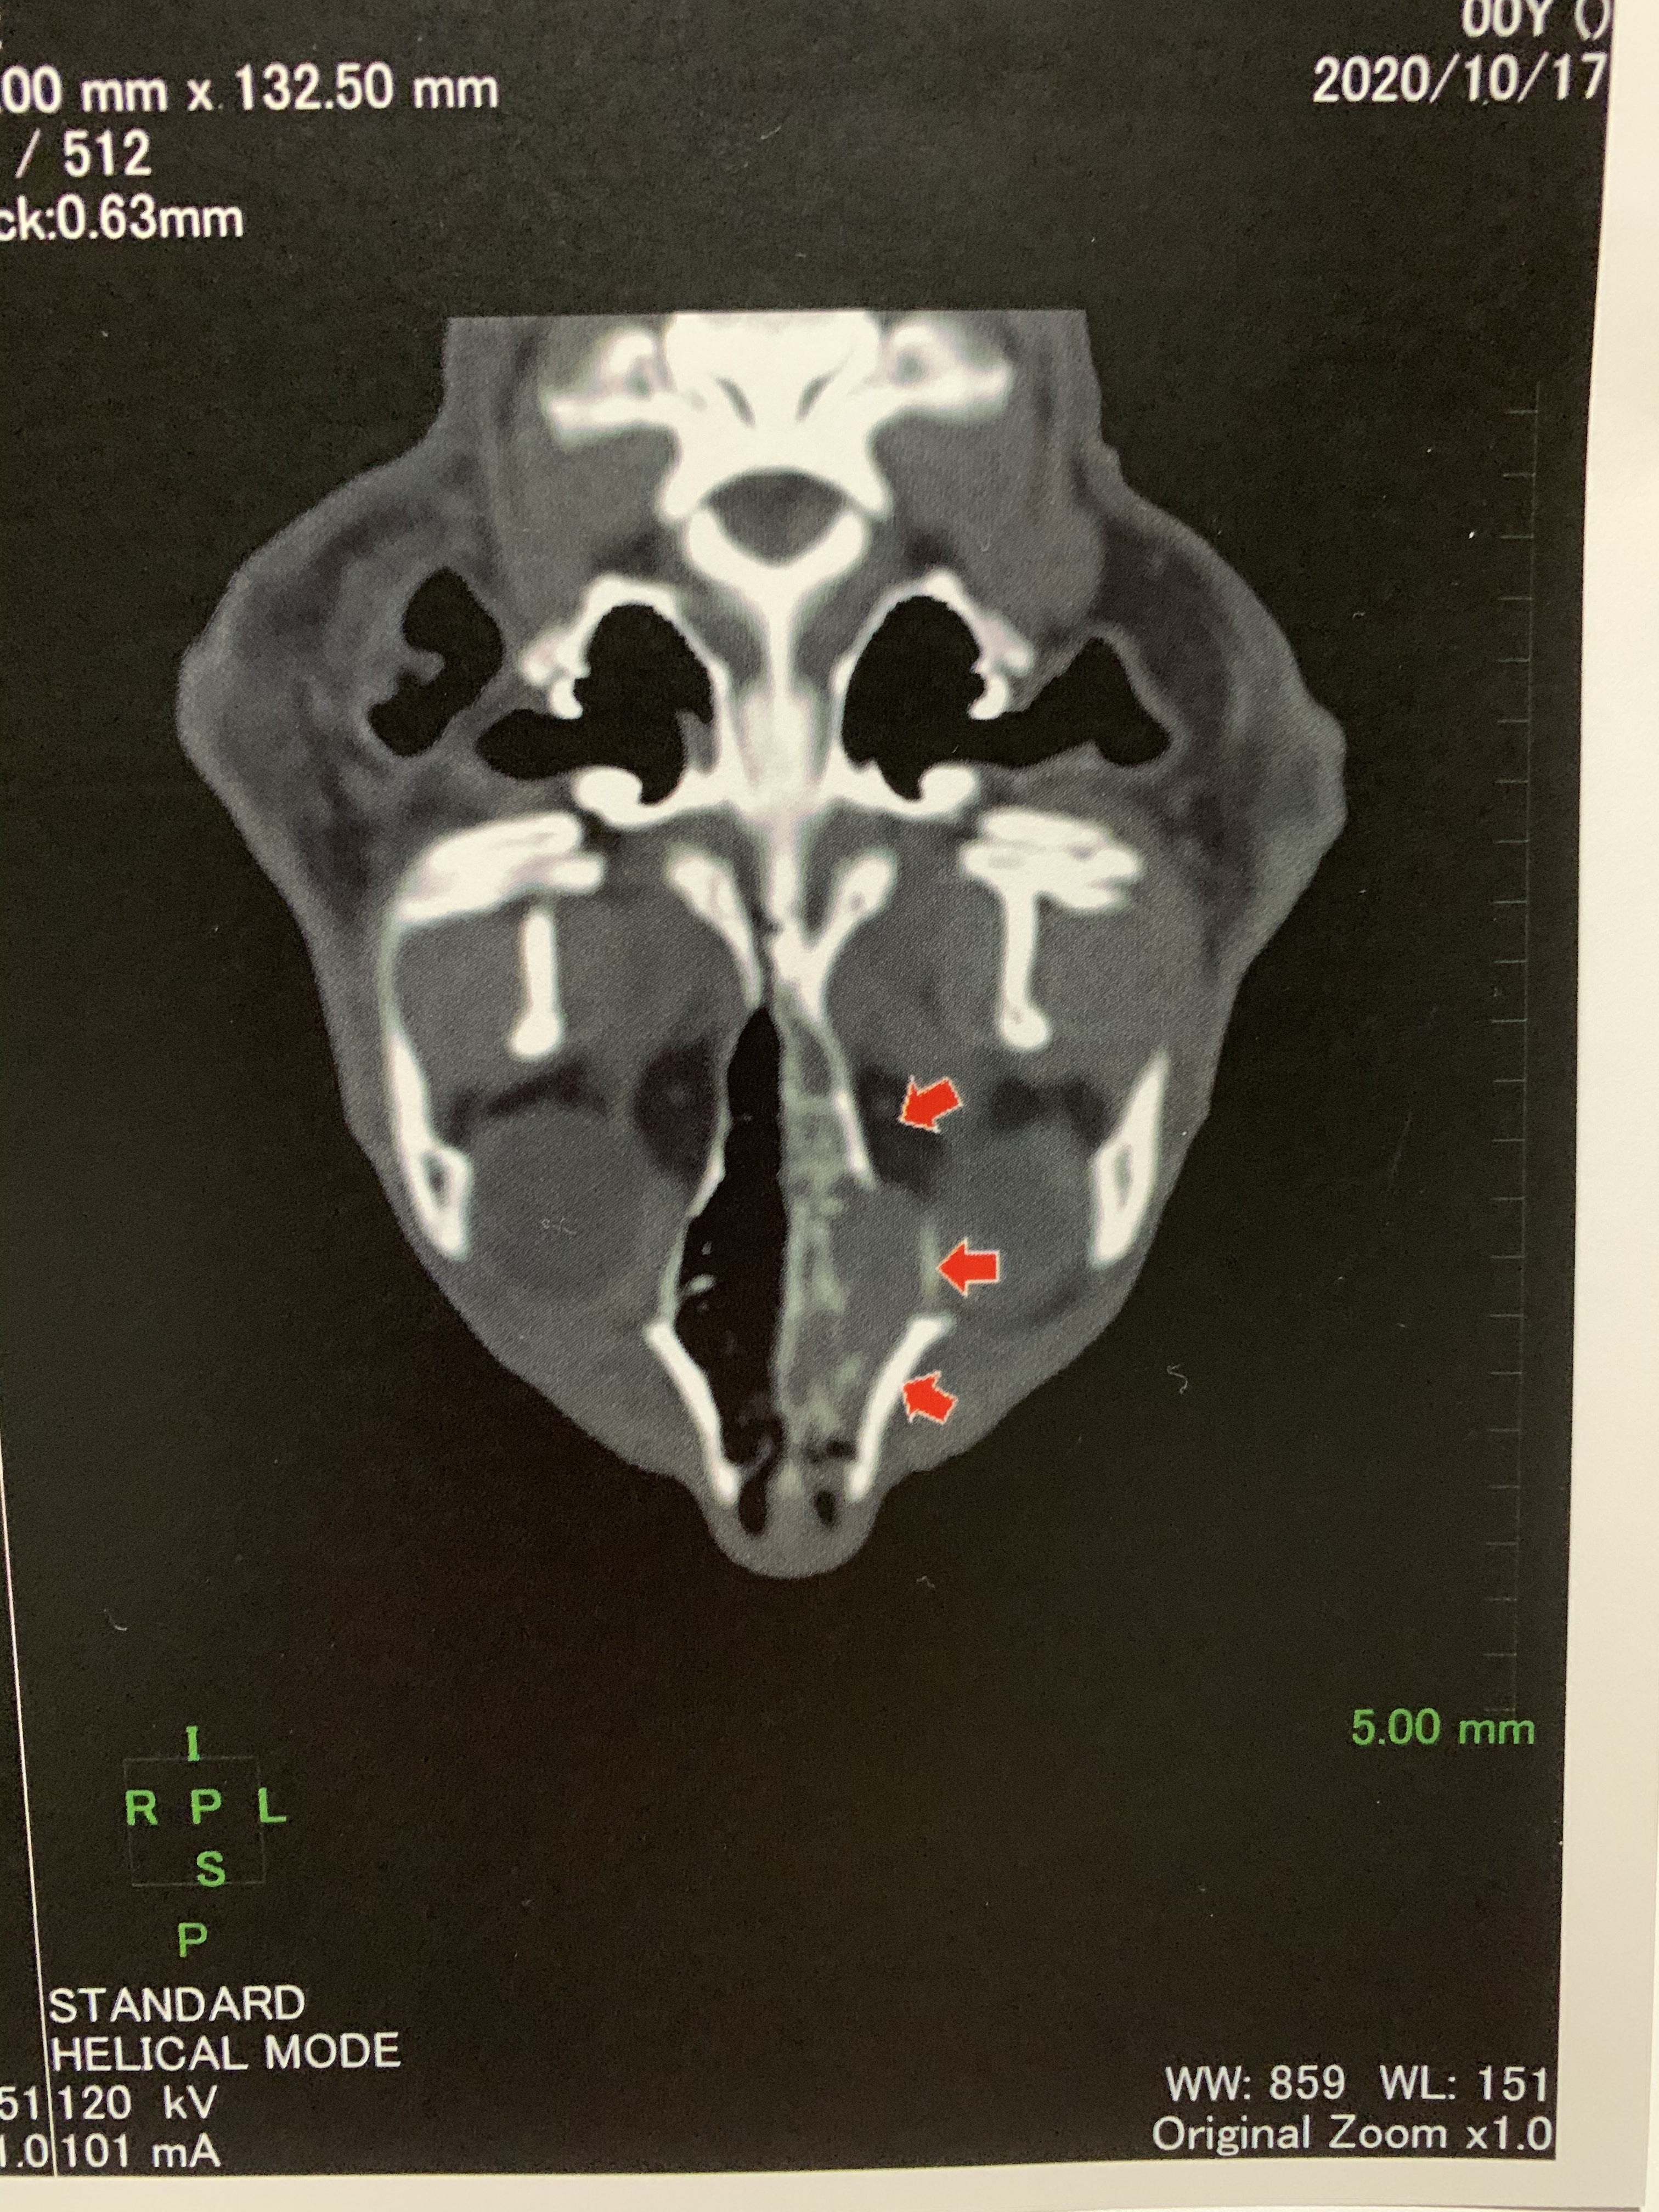

CT画像です

赤い矢印のところが腫瘍です。画像では左右逆になっています。右の鼻腔は黒く空気が通る隙間があるのですが、左は灰色で覆われています。